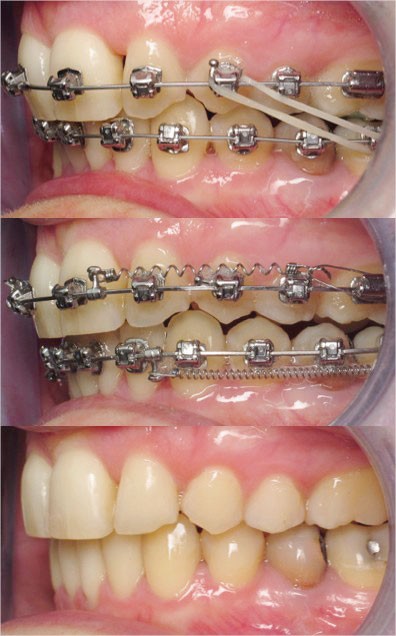

Un appareillage Damon métal a été mis en place, réalisé à partir d’un set up numérique Insignia pour obtenir un contrôle précis des torques et de la forme d’arcade et réduire le temps de finition grâce à un collage indirect très précis.

De larges surélévations postérieures étalées ont été mises en place et la patiente a porté des élastiques précoces suivant les principes de la technique Damon. Les 14 et 24 rempliront le rôle des 13 et 23.

L’objectif, en utilisant la technique Insignia est de réduire le temps de traitement de 28 à 18 mois avec 12 rendez-vous (fig. 5 à 14).

Les objectifs de traitement ont été remplis. Nous avons observé un excellent contrôle du torque et une absence de perte de l’occlusion postérieure grâce à la technique Insignia.